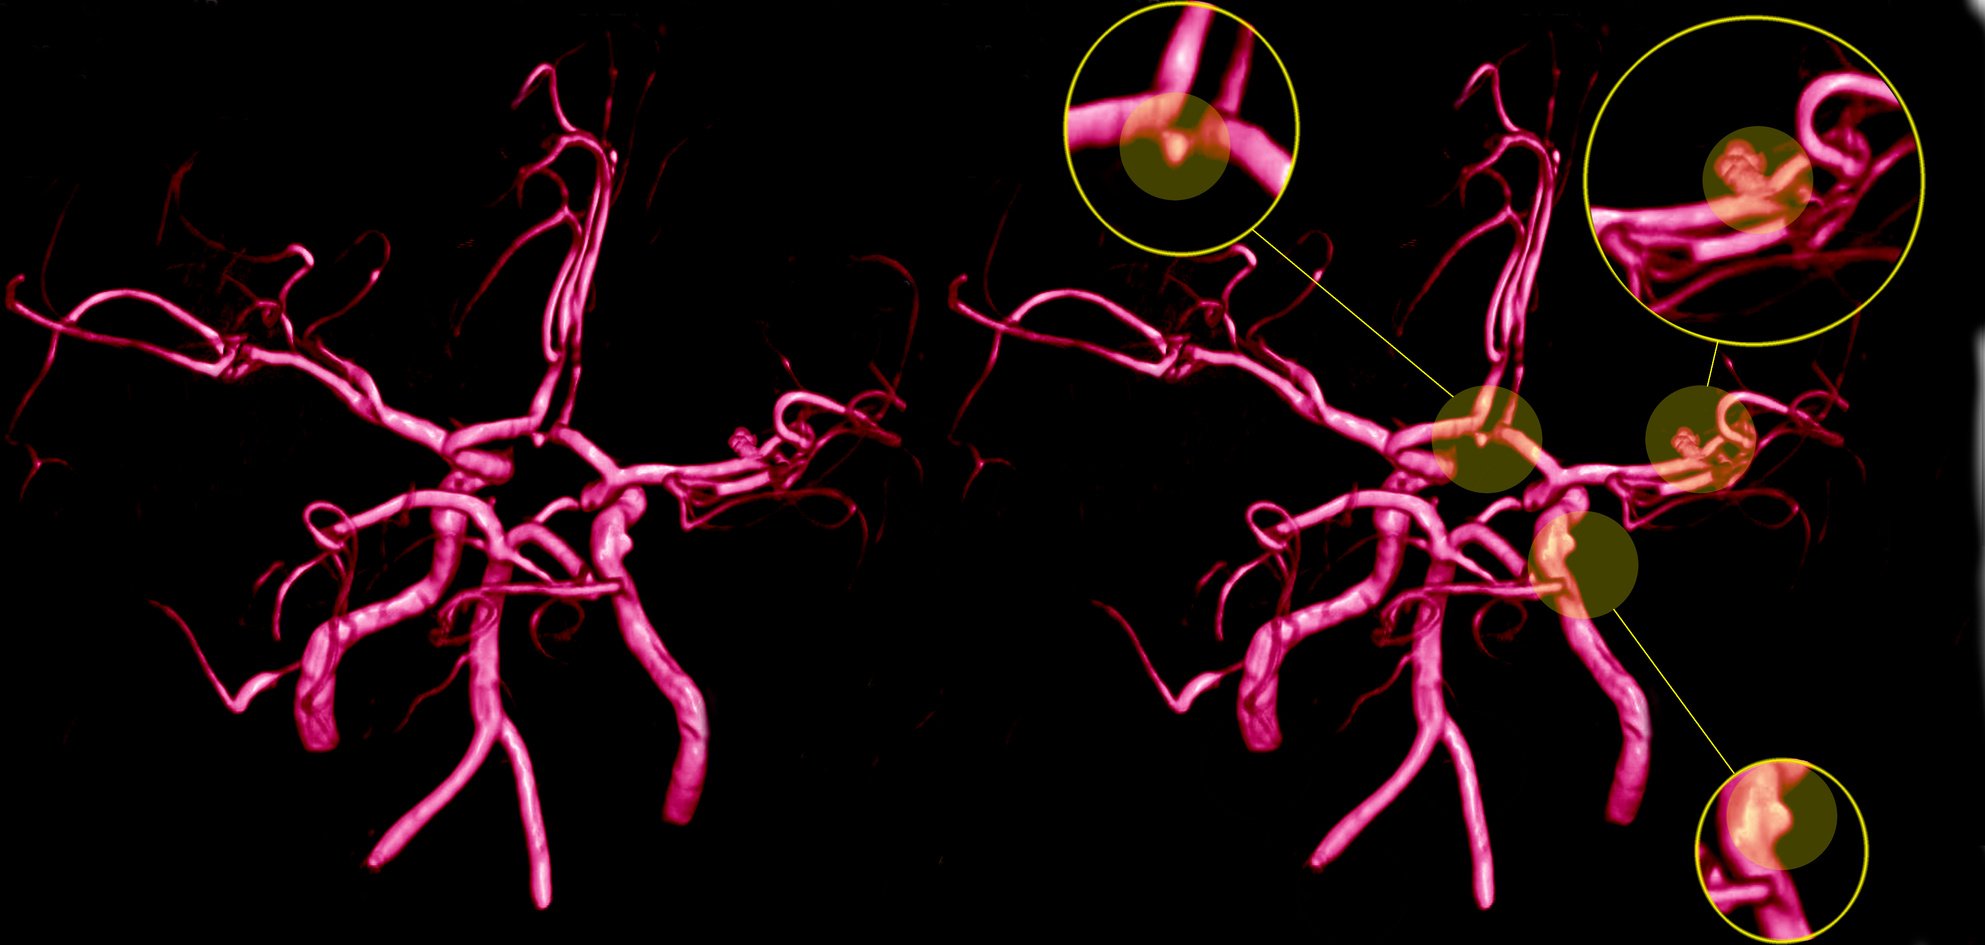

Aneurismas cerebrais

Os aneurismas cerebrais são dilatações patológicas que na maioria das vezes causam fragilidade nos vasos podendo causar sangramentos cerebrais graves.